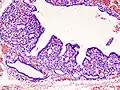

Hyperthyroidism is one of the most common endocrine conditions affecting older domesticated housecats. In the United States, up to 10% of cats over ten years old have hyperthyroidism.[61] The disease has become significantly more common since the first reports of feline hyperthyroidism in the 1970s. The most common cause of hyperthyroidism in cats is the presence of benign tumors called adenomas. 98% of cases are caused by the presence of an adenoma,[62] but the reason these cats develop such tumors continues to be studied.

The most common presenting symptoms are: rapid weight loss, tachycardia (rapid heart rate), vomiting, diarrhea, increased consumption of fluids (polydipsia), increased appetite (polyphagia), and increased urine production (polyuria). Other symptoms include hyperactivity, possible aggression, an unkempt appearance, and large, thick claws. Heart murmurs and a gallop rhythm can develop due to secondary hypertrophic cardiomyopathy. About 70% of affected cats also have enlarged thyroid glands (goiter). 10% of cats exhibit "apathetic hyperthyroidism", which is characterized by anorexia and lethargy.[63]